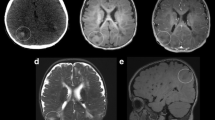

In all but one patient, typical neuroglial hamartomas (tubers) could be identified, consisting of cortical architectural disarray with enlarged, dysmorphic neurons (TSC cells, Fig. 1b) which were variably labeled with neuronal markers (Neu-N, synaptophysin, neurofilament protein, MAP-2) and the glial marker GFAP. Additional immunostains for hamartin, tuberin, and pS6 also labeled the cytoplasm of enlarged, dysmorphic cells in all cases (Fig. 1g, h). A CD34 immunostain demonstrated labeling of a single enlarged neuronal-type cell in a granular cytoplasmic fashion in one case, as previously described for ganglion cells in ganglioglioma [6, 10]. In the other four cases, CD34 stained vascular endothelia only (Fig. 1f).

Case 3: MRI revealed multifocal bihemispheric cortical/subcortical regions of hyperintensity on T2 (a). Histologically, there were large “balloon cells” (arrows) typical of a “tuber” (b, H&E, 40×), but there was also striking cellularity (c, H&E 40×). There were cells resembling gliomatosis-like cells with elongate irregular nuclei (arrows), which were labeled by a GFAP immunostain (d, GFAP 40×). LCA revealed a scattered inflammatory infiltrate (e, 40×). CD34 labels endothelial cells only (f, 40×). TSC cells are highlighted in the background of infiltrating cells by the pS6 immunostain (g, 20×). Tuberin also marks TSC cells (h, 40×)

In addition, in each patient specimen there was an infiltrate of atypical, irregularly shaped gliomatosis-cerebri-like cells with mostly elongate, but in some cases focally oval to round nuclei. These cells resembled “naked nuclei” with no discernible cytoplasm on H&E stains which were seen to infiltrate among cortical neurons in well-ordered as well as dysplastic areas, and were also present in the underlying white matter (Figs. 1c, 2a). Immunohistochemical characteristics of these infiltrates are summarized in Table 2.

There was immunopositivity of a portion of these cells with GFAP in three cases, but no labelng with Neu-N, synaptophysin, neurofilament protein, MAP-2, CD34, hamartin, tuberin, pS6, CD68 (Kp-1) and CD45 (LCA) immunostains (Figs. 1d–h, 2d, f), while the MIB-1 labeling index was low (<1%) in one case, the other four cases had MIB-1 labeling indices ranging from 8 to 21% (Fig. 2c). P53 immunostains revealed focal immunopositivity in two cases (Fig. 2e). However, in one of these, there was also labeling of TSC cells with p53 (Fig. 2e).